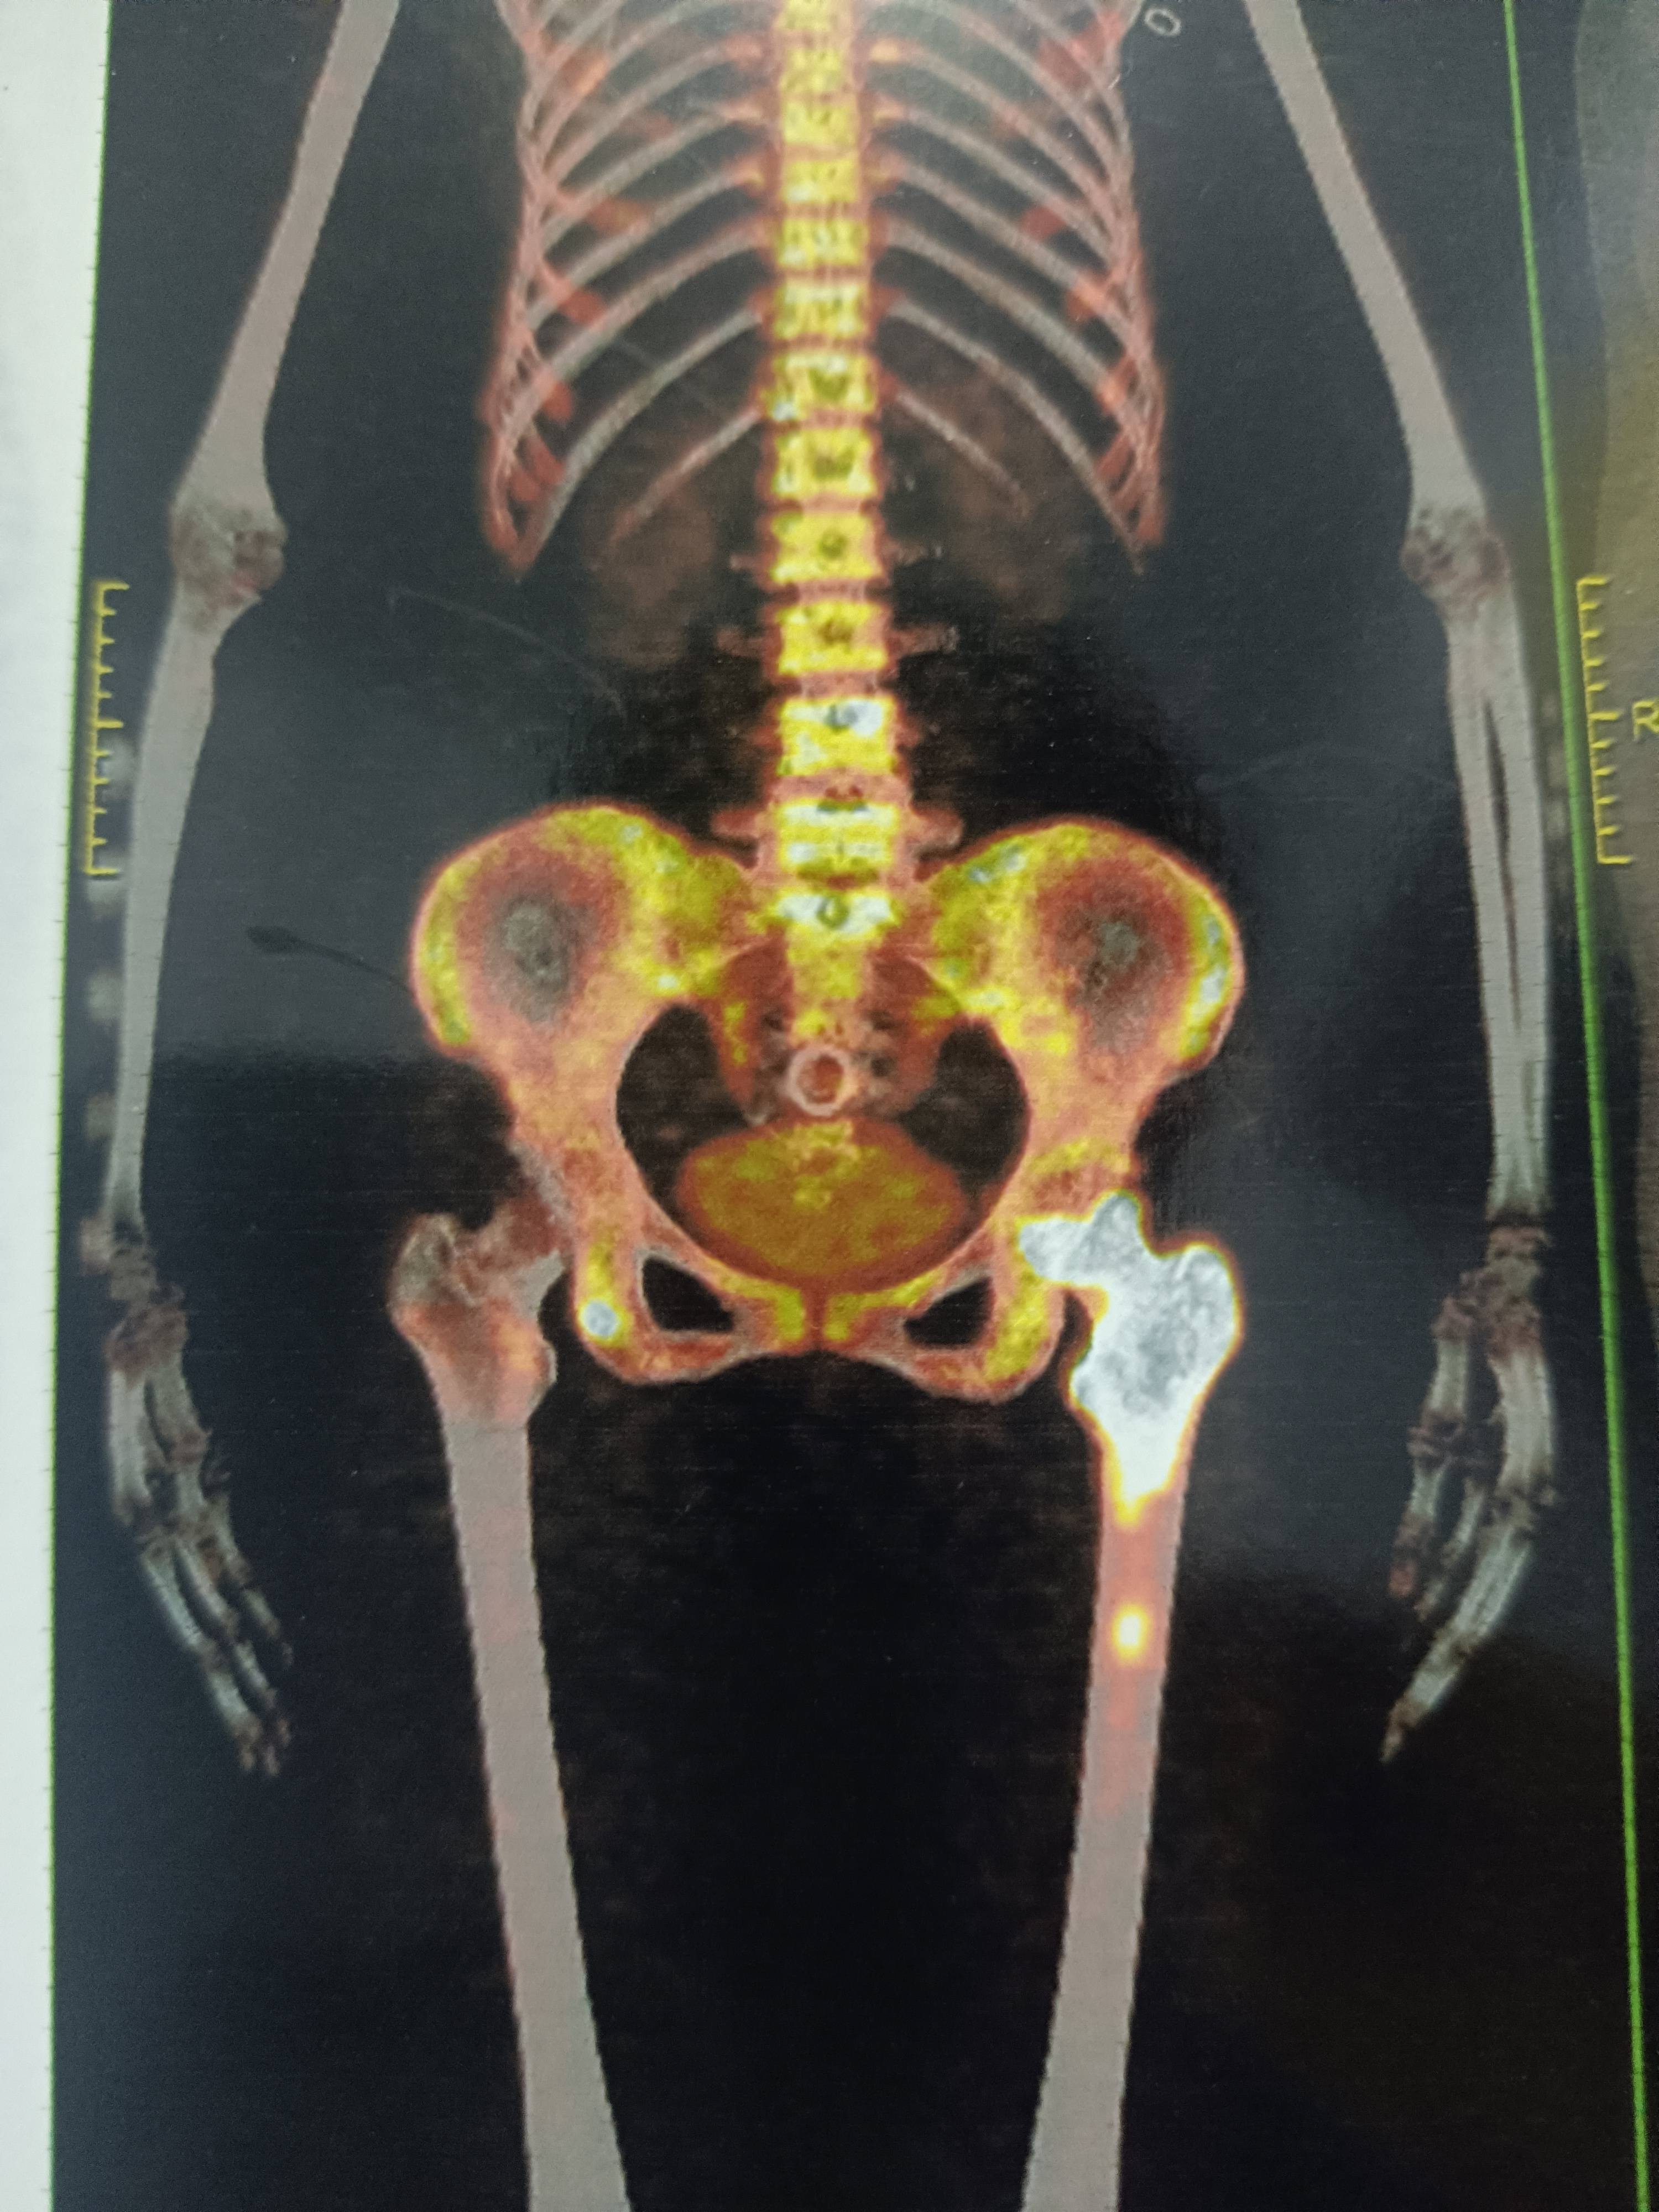

骨转移,髋关节股骨置换

去年与5月份查出多处骨转移,其中股骨上端比较严重,骨头钙质流失坏S,痛得比较厉害,做了局部的放疗,慢慢不痛,也就没有去进一步干涉,如果当时这个时候做一个骨水泥填充,估计会好一点,但是没有去干预!今年5月份又开始痛了,家里人一直催着去医院看看该如何治疗,挂了个骨肿瘤科看,医生看片子就就皱着眉头了,说我这个要尽快处理,要不然脚会断掉,到时就更不好弄了,说我身体还许可,让我做髋关节置换!和家人商量了一下,觉得还是治疗的好,不用去想自己还能活多久,最起码熬过了手术,生活质量能提高!有坚持,就有希望!